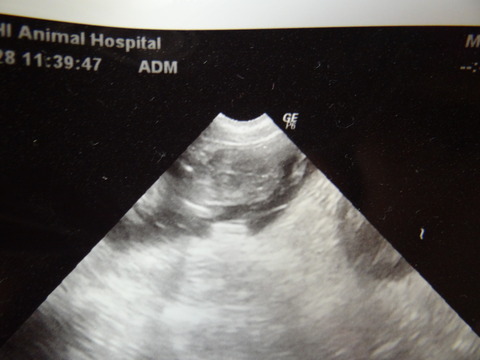

ふぃっちゃんの中身。笑

心臓も元気で背骨ももう見えましたよ~~

良く寝て良く食べて、喧嘩売ってます!